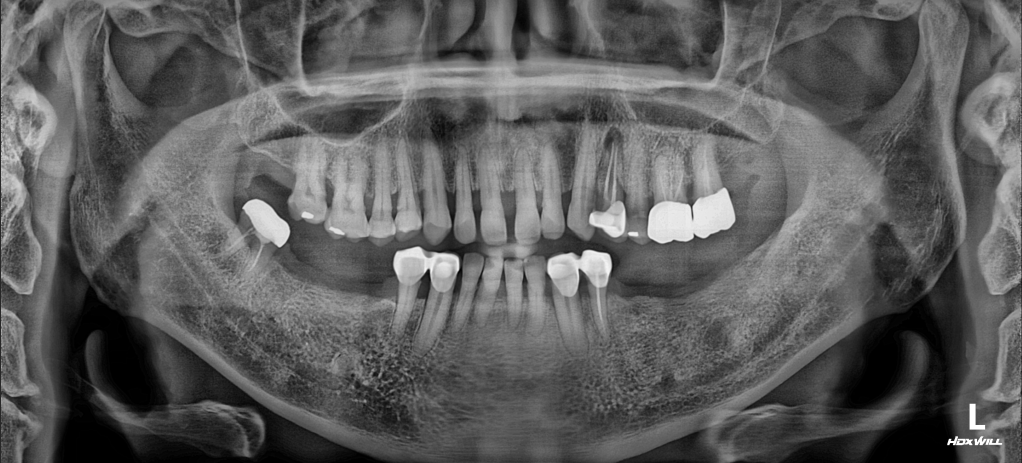

Severe Periodontitis and Alveolar Atrophy secondary to failing removable prosthetics in a female patient in her 50s. Systematic VDO elevation and transition to a maintainable, fixed implant-supported environment.

Read More